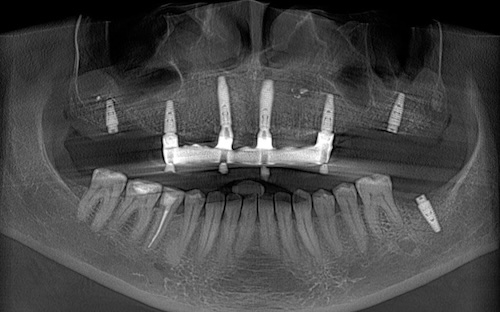

Сканы КТ имплантации зубов, 2026-04-18

Скан КТ, 2026-04-18

Сканы КТ имплантации зубов, 2026-04-18

Скан КТ имплантации зубов, 2026-04-17

Сканы КТ имплантации зубов, 2026-04-18

KT: имплантация зубов DentalKnysh, 2025-01-03, сканы

KT: имплантация зубов DentalKnysh, 2025-01-03, сканы

KT: имплантация зубов DentalKnysh, 2025-01-03, сканы

КТ имплантации зубов в DentalKnysh (10 имплантов), 2023-11-03

С 2023-09-05 по 2023-09-09 сканы КТ от 6 до 12 имплантов в DentalKnysh (4 фото):

Синуслифтинг и имплантация зубов, 6 имплантов, all-on-6, КТ скан 1, 2023-08-31

Фото отчет Имплантация зубов, 6 имплантов, КТ скан 3, 2023-08-31

Фото отчет Имплантация зубов, 8 имплантов, all-on-4, КТ скан 1, 2023-08-31